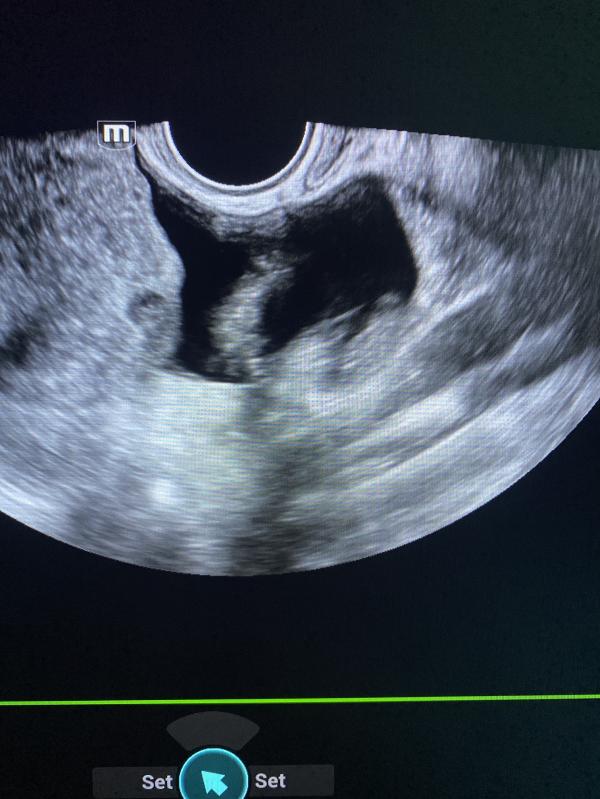

на последующих фимбрии маточных труб 🤍❤️